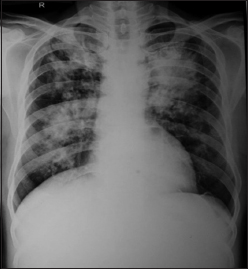

A 65-year-old male, smoker presented with complaints of dry cough, chest pain, and low-grade fever for the last 3 months in the pulmonary department. Multifocal dense consolidations involving bilateral lungs fields were discovered on simple chest X-rays [Figure 1]. His vital signs on admission were normal and laboratory results were white blood cells 5400/mm3, hemoglobin 15.2 g/dL, hematocrit 39.2%, platelet 188 k/mm3, and erythrocyte sedimentation rate 5 mm/h. A serology test and culture for mycoplasma and tuberculosis were all negative. Chest and abdomen computed tomography showed multifocal dense consolidations involving bilateral lungs with perihilar predominance and hypodense bilateral adrenal masses [Figure 2]. Bronchoscopic findings were nonspecific.

| Figure 1 Chest X-ray posteroanterior view